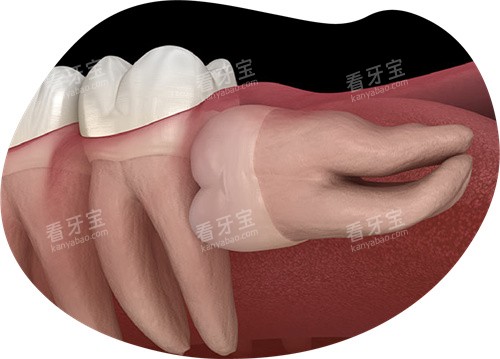

复杂阻生齿(未萌出、靠近神经管):建议综合医院口腔颌面外科。

阻生智齿压迫邻牙导致牙根吸收。

智齿引发颌骨囊肿或含牙囊肿。